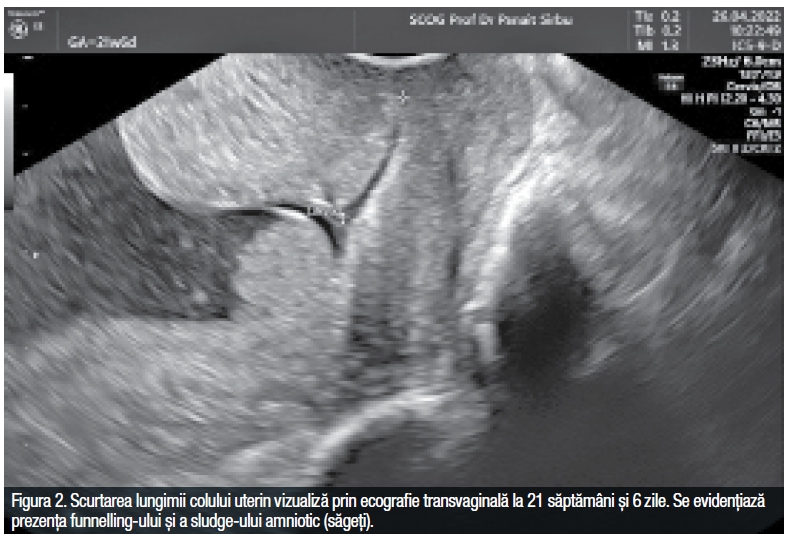

Examinarea ecografică este totodată un instrument foarte important și pentru evaluarea riscului de naștere prematură în sarcinile gemelare, prin măsurarea lungimii colului uterin (ideal prin examinare transvaginală), valoarea cut-off folosită cel mai frecvent fiind de 25 mm între 18 și 24 de săptămâni de sarcină. Atunci când lungimea colului este mai mică de 15 mm managementul trebuie să includă: cerclajul, antibiotice, tocoliză.10 (Figura 2)